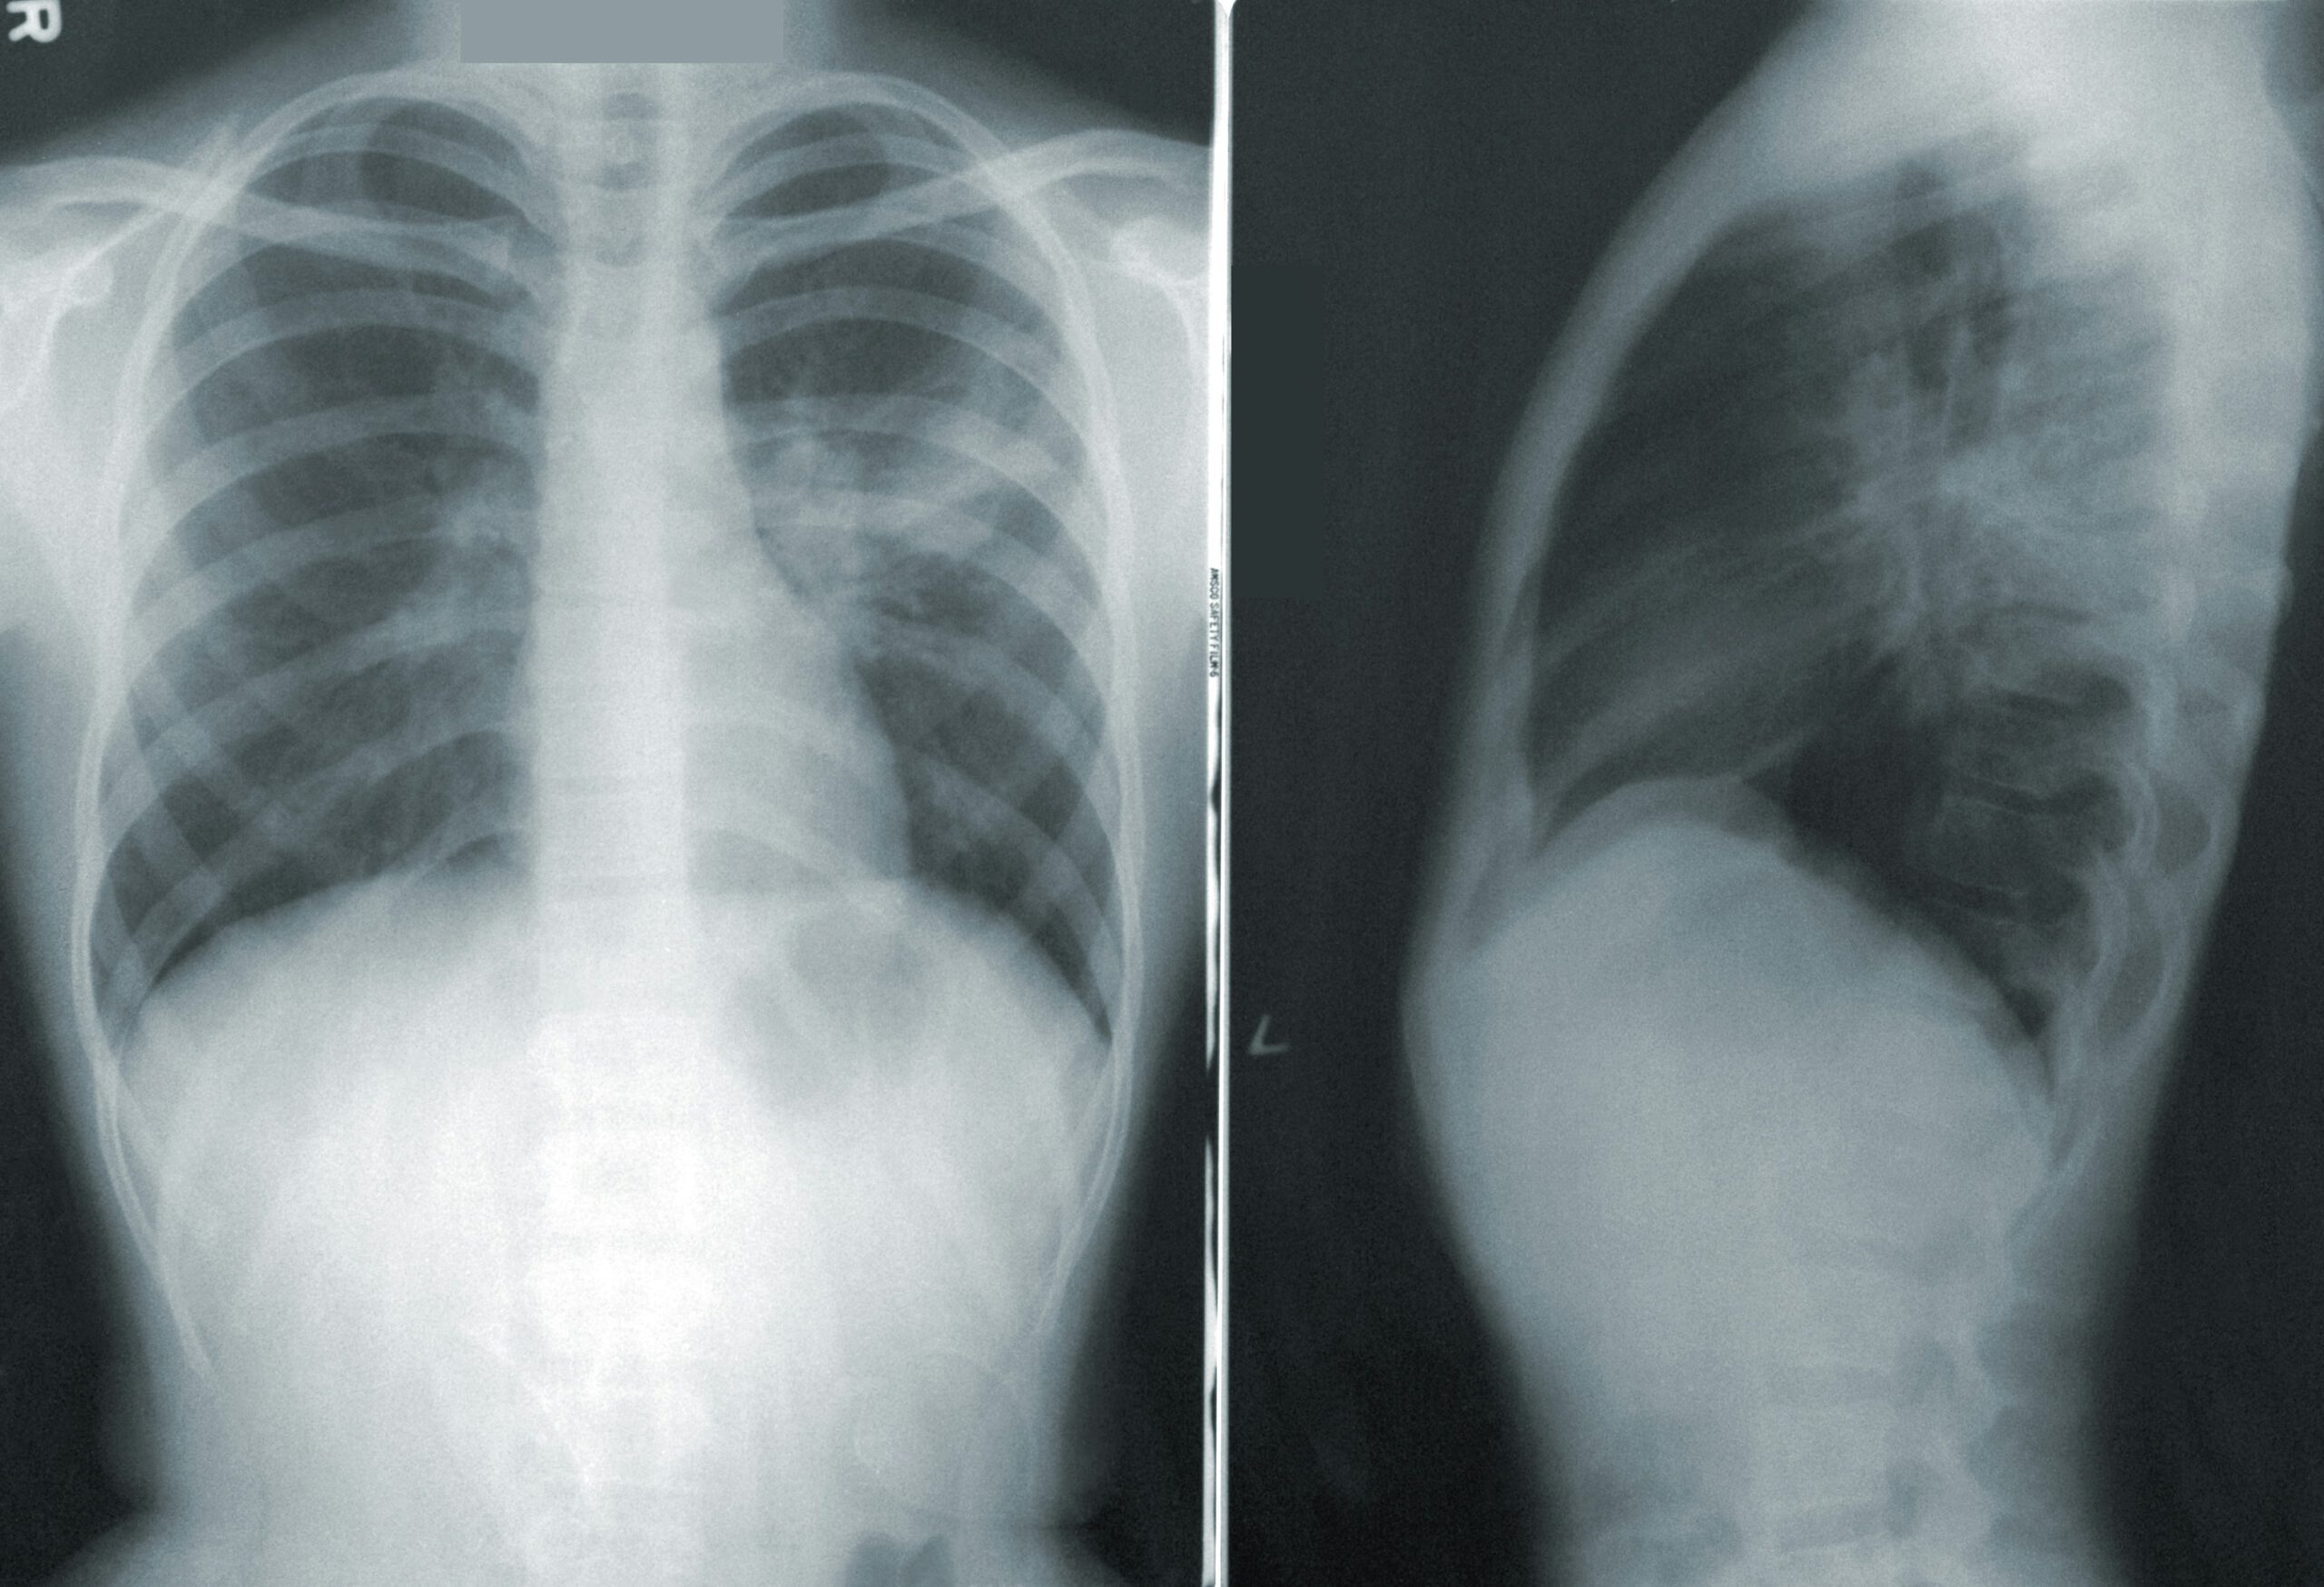

Seit Kurzem gibt es in Deutschland ein kostenübernommenes Lungenkrebsscreening für Menschen mit erhöhtem Risiko. Dieses Angebot kann helfen, Lungenkrebs bereits in einem sehr frühen Stadium zu entdecken – bevor Beschwerden auftreten – und damit die Behandlungschancen deutlich verbessern.

Nach einem persönlichen Beratungsgespräch erfolgt eine Low-Dose-CT-Untersuchung der Lunge. Sie ist: